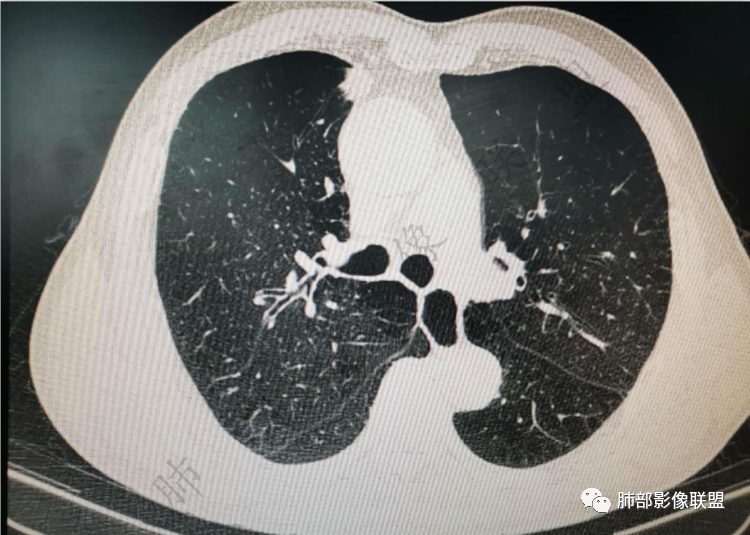

右肺上类圆形叶结节,周边见细软毛刺,增强后呈环形明显强化,内部坏死,邻近胸膜光滑,结合病史2个月明显增大,考虑炎性可能性大。

老年男性,炎性指标略高,肺气肿背景。右肺上叶胸膜下结节,部分边缘平直,部分稍模糊,软长毛刺,血管增粗,病灶中心密度减低,邻近脂肪间隙清晰。考虑炎性肉芽肿或慢性炎症,鉴别鳞癌。

老年男性,炎性指标略高,肺气肿背景。右肺上叶胸膜下结节,部分边缘平直,部分稍膨隆,供血血管增粗,增强扫描病灶中心密度减低,呈环形强化,邻近脂肪间隙清晰。考虑炎性肉芽肿或慢性炎症,鉴别鳞癌。

右肺上叶前段胸膜下结节,边缘分叶毛刺,血管集束,支气管截断,纵膈胸膜牵拉,内乳动脉增粗,密度不均,中央可见坏死,两个月短期随访结节有增大,考虑恶性,腺癌。鉴别结核。

肺气肿背景,右肺上叶纵隔旁胸膜下结节,有血管集束,支气管堵塞,内乳动脉增粗,增强不均匀强化,内可见低密度区。考虑为恶性可能性大

老年男性,肺气肿背景,右肺上叶胸膜下弧立实性不规则结节,密度不均,其内低密度坏死影,支气管似有截断,血管集束,2月复查明显增大,考虑恶性,鳞癌可能大,鉴别炎性肉芽肿

老年男性,炎性指标略高。影像表现右肺上叶胸膜下结节,膨胀性生长部分边缘平直,边界清晰,病灶可见血管集束征,近段支气管阻断?增强扫描病灶中心密度减低,低密度区边界模糊,外围环形强化。老年性,不能排除恶性病变,周围性鳞癌,其次才考虑炎性肉芽肿或慢性炎症

老年男性,肺气肿背景,右肺上叶前段胸膜下结节,部分边缘毛糙,血管集束增粗,支气管似有截断,胸膜牵拉,结节密度不均,两个月随访结节有增大,考虑恶性,肺癌可能;另右肺上叶后段肋胸膜区小片状类结节影,考虑炎性可能。

右肺上叶前段胸膜下结节,近段支气管截断,血管伸入结节内,密度不均,同侧临近内乳动脉增粗,不均匀强化,肺气肿背景,两月明显增大,考虑低分化鳞癌,隐球菌代排

老年男性,无症状,炎性指标增高。肺气肿背景,右肺上叶前段结节,边缘部分平直部分澎隆,血管集束,支气管至病变边缘似截断,近端扩张。增强环形强化,中心坏死。两月内病灶增长太快,考虑炎性肉芽肿,慢性脓肿?结核?癌待排。

肺气肿背景

支气管变形、壁增厚,提示慢性支气管炎症

边缘平直

宽基底与胸膜相连,附近胸膜增厚,糊墙

内部有低强化区,边界尚清

还是支持炎性放前面,恶性待排